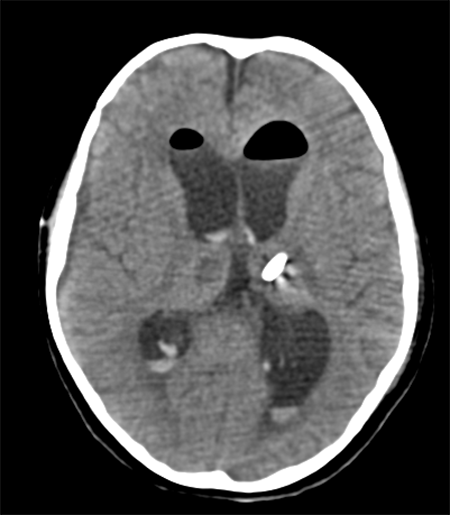

Caso ilustrativo n°4: Houkin tipo 4(Figura 4)

Paciente de 4 meses de vida, fue llevada a la guardia por vómitos intermitentes, posteriormente agregó sensorio alternante, tendencia al sueño. Al examen físico se evidenció perímetro cefálico aumentado, fontanela llena, estrabismo convergente ojo izquierdo intermitente y retraso de adquisición de pautas madurativas: no sigue objetos y sin sostén cefálico. Se realizaron múltiples punciones transfontanelares en otra institución y se derivó a nuestro centro. Ingresó en la madrugada y se realizó cirugía de colocación de drenaje ventricular al exterior. Posteriormente a las 12 hs presentó descompensación, con deterioro del sensorio. En imagen control por tomografía se evidenció ventrículo ipsilateral a lesión colapsado y herniación subfalcial, por lo que se realizó cirugía de urgencia de exploración y exéresis. Evolucionó favorablemente.

Se consideró Houkin tipo 4, ya que se podría haber evitado dicho deterioro si se operaba directamente el tumor.

Figura 4: Imagen por Tomografía Cerebral computada que muestra catéter en cavidad ventricular, con herniación subfalcial de la misma. Se observa diástasis global de suturas craneanas, edema cerebral y lesión ocupante de espacio sólido-quística intraventricular derecha.